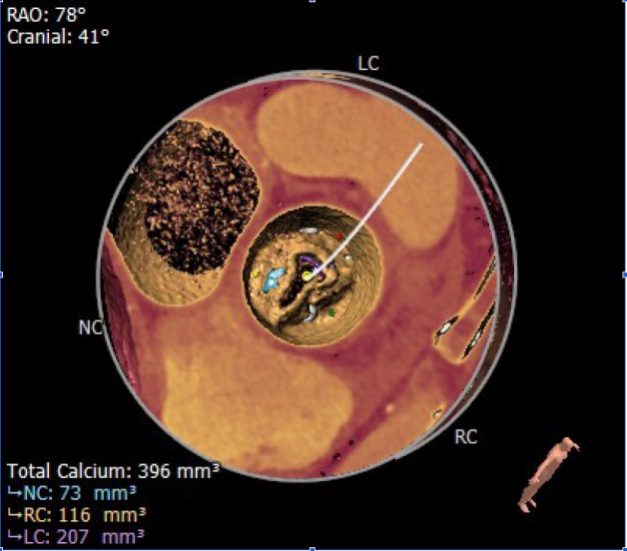

术前CT评估

1.患者主动脉瓣三叶式,瓣叶基本等大,瓣叶增厚,游离缘重度钙化,钙化至窦底可见。

2.患者主动脉瓣环周长折算直径约24.5mm。

3.患者双侧冠脉开口高度尚可:LCA:10.4mm,RCA:13.3mm。

4.患者术中最佳造影角度RAO:19°,CAU:24°。

5.升主动脉增宽。

瓣环直径:24.5mm

升主动脉直径:45.7mm

左冠开口高度:10.4mm

右冠开口高度:13.3mm

主动脉瓣环及瓣叶总钙化积分:396mm³

术中最佳造影角度RAO:19°,CAU:24°